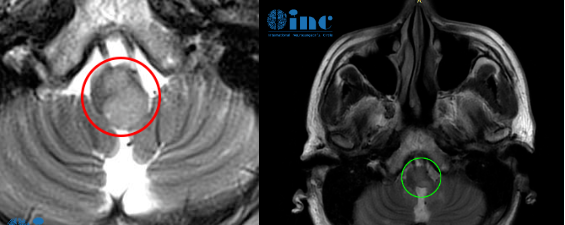

- 文章标题:"低级别胶质瘤”术后竟是胶质瘤4级